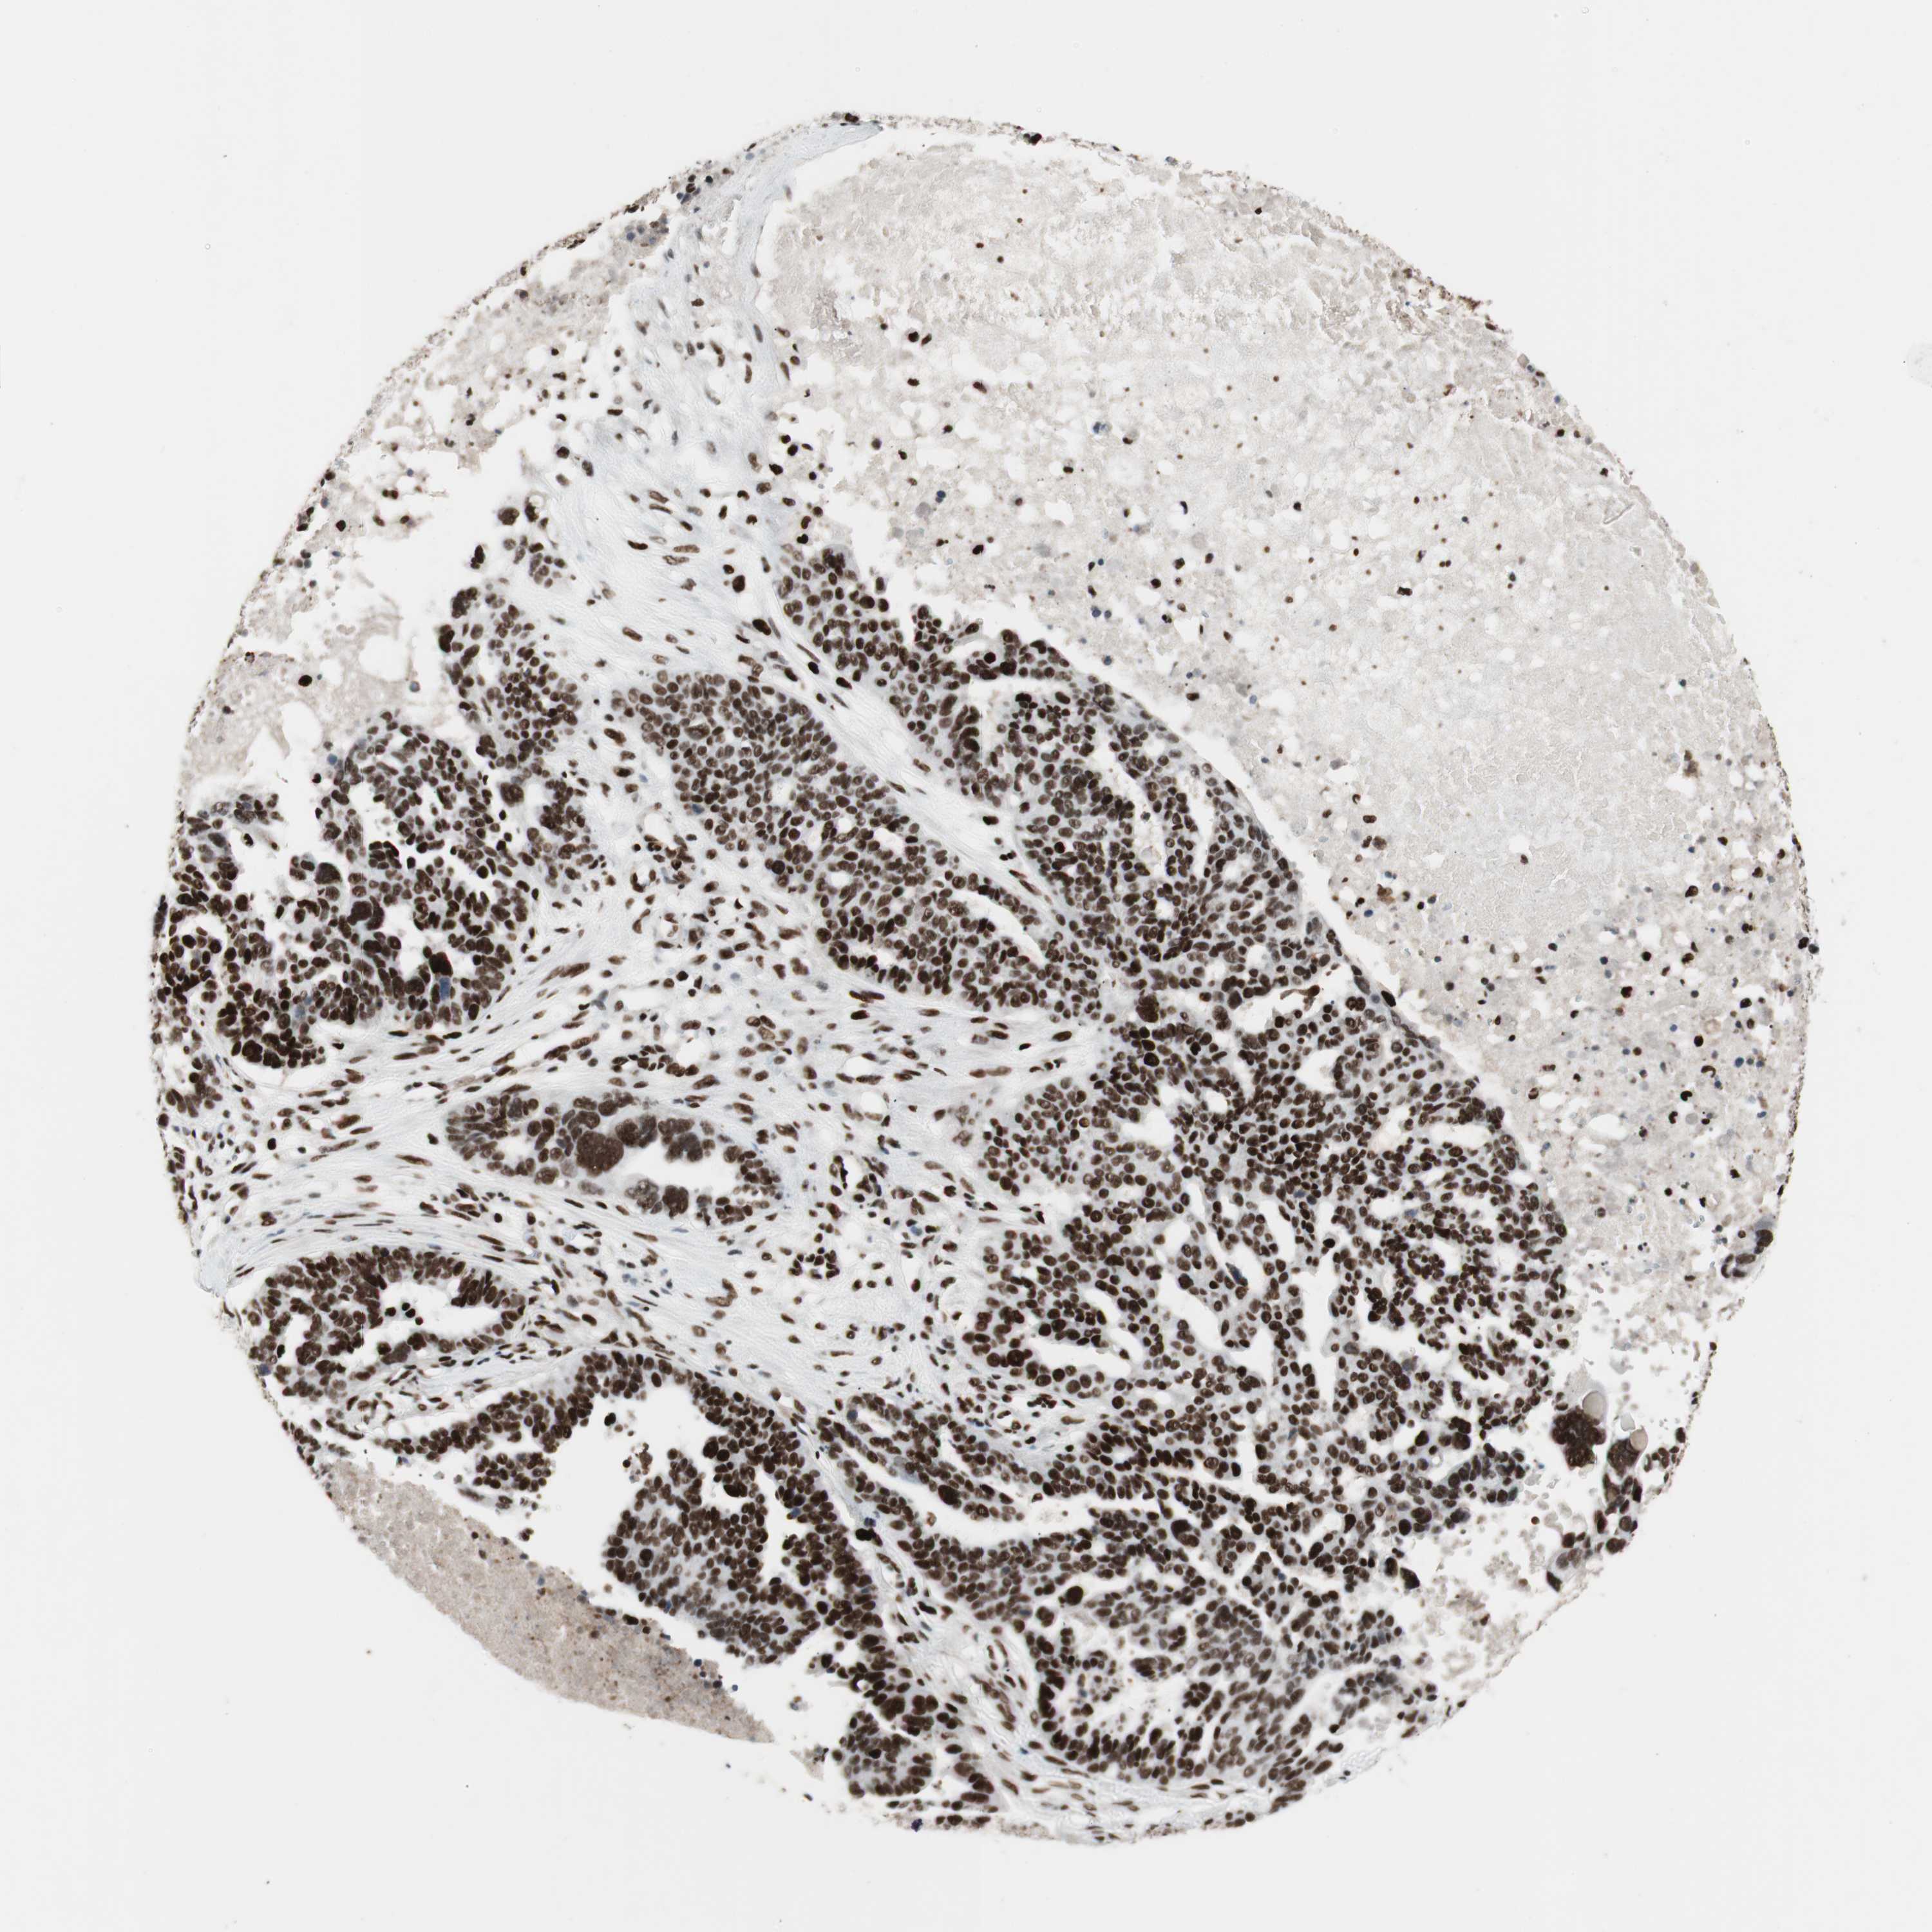

OVARIAN CANCER - Protein expressioni

A mouse-over function shows sample information and annotation data. Click on an image to view it in a full screen mode. Samples can be filtered based on level of antibody staining by selecting one or several of the following categories: high, medium, low and not detected. The assay and annotation is described here.

Note that samples used for immunohistochemistry by the Human Protein Atlas do not correspond to samples in the TCGA dataset.

Antibody stainingi

Antibody staining in the annotated cell types in the current human tissue is reported as not detected, low, medium, or high, based on conventional immunohistochemistry profiling in selected tissues. This score is based on the combination of the staining intensity and fraction of stained cells.

Each image is clickable and will lead to virtual microscopy that enables deeper exploration of all samples and also displays staining intensity scores, fraction scores and subcellular localization as well as patient and tissue information for each sample.

Antibody HPA012510

Antibody CAB008388

Staining

High

Medium

Low

Not detected

Intensity

Strong

Moderate

Weak

Negative

Quantity

>75%

75%-25%

<25%

None

Location

Nuclear

Cytoplasmic/membranous

Cytoplasmic/membranous,nuclear

Cystadenocarcinoma, serous, NOS

Carcinoma, endometroid

Cystadenocarcinoma, mucinous, NOS

Carcinoma, NOS